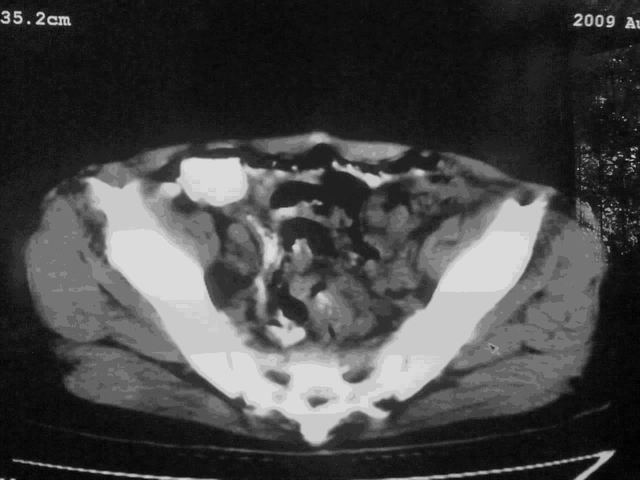

我这个考考大家眼力,看看是升结肠ca还是降结肠ca

下面的是4小时后的,

好象是横结肠占位肝转移,胰头占位?【伙计,您的片也真够意思】

伪影太多,考虑降结肠癌伴肝转移,胆囊炎

伪影太多,考虑升结肠癌伴肝转移,胆囊炎

片子质量差了点,好像是降结肠

考虑升结肠癌伴肝转移;胆囊炎。

结肠占位并肝及腹膜后淋巴结转移。

明确考眼力!考虑降结肠癌伴肝转移可能性。

考虑升结肠癌伴肝转移;胆囊炎

伪影太多,考虑降结肠癌伴肝转移,胆囊炎。